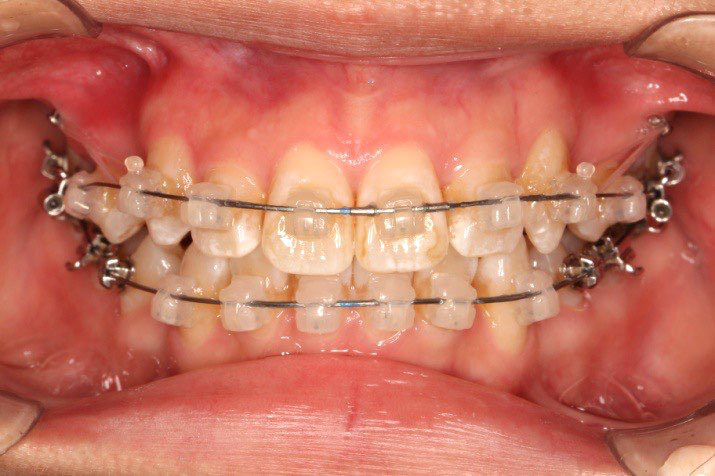

• 磨牙,尖牙I类关系,中线齐

• 上下牙列中度拥挤

• 上下前牙唇倾

2018.11.14  术后磨牙尖牙I类关系,中线齐,覆合,覆盖正常

Post-TXPRE-TXPost-TXNormFMIA°47°57.555.0SNA°77.7°76.883.0SNB°70.2°73.780.0ANB°7.5°3.13.0FMA° 29.828.026PFH/AFH70.5°65.970Z Angle°50.3°64.477U1-FH113.0103.7110.0 IMPA°103.291.197.0U Lip tos’ line6.3 mm3.25.0L Lip to s’ line3.9 mm1.03.0OP-FH1212.615